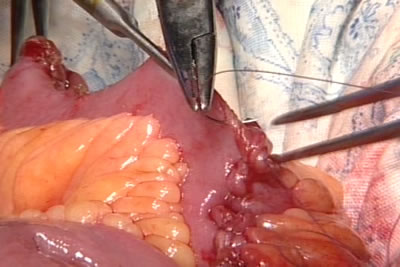

Брыжейка тонкого кишечника рассечена. Тонкий кишечник на

небольшом расстоянии освобождается от жировой ткани брыжейки.

Гемостаз сосудов брыжейки. Нужный участок тонкой кишки

отсекается. Из выделенного сегмента, который остается на

брыжейке, будет сформирован новый мочевой пузырь низкого

давления. На проксимальный и дистальные концы оставшегося

кишечника будет наложен анастомоз.

Кишка детубулизируется - рассекается по свободному от брыжейке

краю.

Формируется мочевой резервуар низкого давления из тонкого

кишечника.

Новый мочевой пузырь.